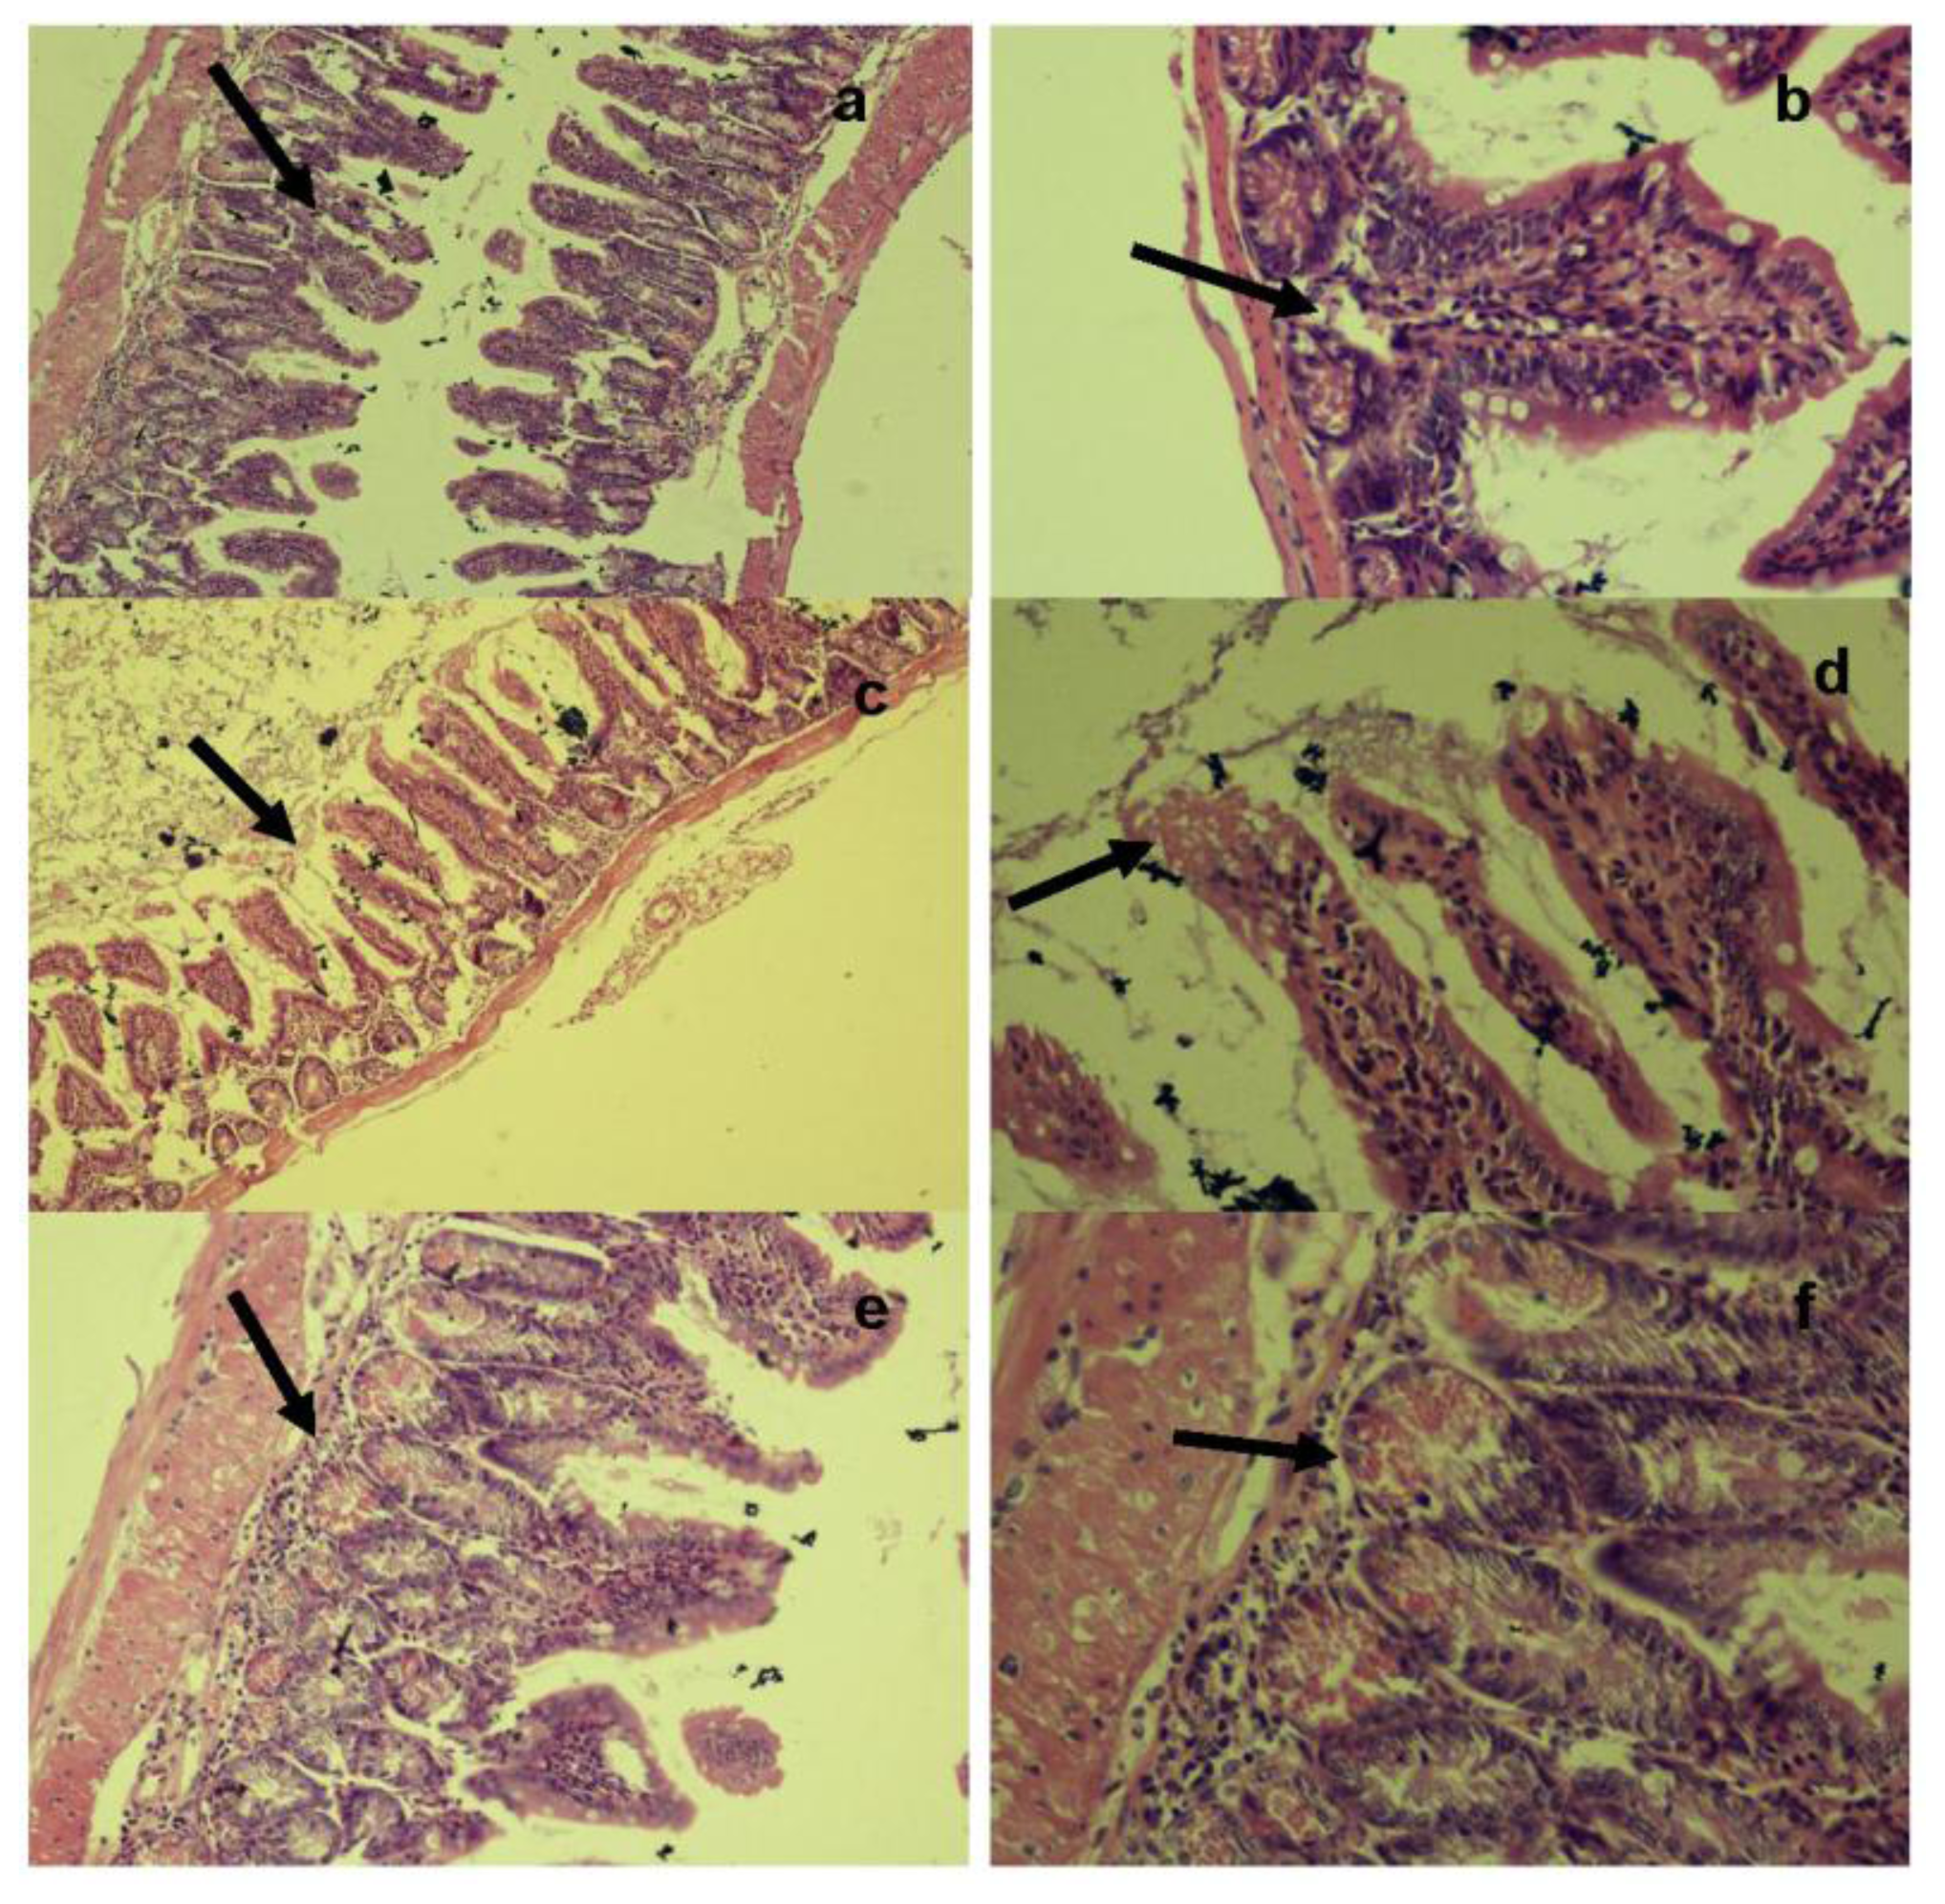

Histopathological examination of the ileum tissues of mice infected with unstressed Salmonella Typhimurium showed increased inter-villus gaps (Figure 6) with mild lymphoid tissue depletion and hyperplasia of Paneth cells at 6 h post-infection. Figure 6a shows increased inter villus gap (H & E × 280) with an increased number, size and density of Paneth cells (Figure 6b) (H & E × 560). By 12 h post-infection, the tips of villi were observed to dissolve, giving a “spire” appearance with loss of nuclei and merging of cytoplasm and basement membranes. There was lympholysis with depletion of lymphocytes (Figure 6c) (H & E × 280) as well as merging of cytoplasm and basement membrane (Figure 6d) (H & E × 560). At 24 h, the villi appeared shrunk and apart (Figure 6e) (H & E × 280) with grossly distended crypts and excess apoptosis of Peyer’s patch (Figure 6f) (H & E × 560). Advanced depletion of ileum mucosa was observed with villi that were shrunk and more widely spaced than in normal tissue. There was also a marked mucosal and crypt dissolution, with substantial apoptosis of lymphoid cells in the lamina propria and Peyer’s patch.

Figure 6.

Histopathological examination of ileum tissue of mice infected orally with 2.2 × 107 CFU of unstressed Salmonella Typhimurium at (a,b) 6 h, (c,d) 12 h and (e,f) 24 h post-infection.